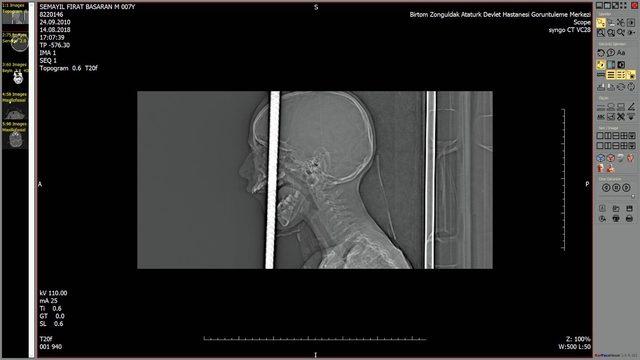

Doç. Dr. Şansel Gül ise üst damaktan giren yaklaşık 1 metre uzunluğundaki demir çubuğun sol ön kafa tabanını delerek dışarı çıktığını söyledi. İlk olarak dışarıda kalan 40 santimlik bölümün 3 santim kalana kadar AFAD tarafından kesildiğini anlatan Doç. Dr. Gül, "Kafa kemiği parçalanmıştı. Temel prensiplere bağlı kalarak burayı genişlettik. Çubuk bu şekilde rahatlatıldı. Ameliyata bölüm başkanımız da dahil oldu. Doktor Emrah da çubuğu boşladıktan sonra çubuğu çektik. Çocuğumuz şimdi yoğun bakımda. Bilinci açık görünüyor, fakat zaman içinde neyi kaybettiğini gözlemleme şansımız olacak. Şu an enfeksiyon riski var. Bununla mücadele ediliyor. Onlarca insanın emeği var. Zaman bize neler olacağını gösterecektir. Ana besleyici damarlara hasar vermemiş olmaması bizim için önemliydi" diye konuştu.

Hastane Başhekimi Doç Dr. Bekir Hakan Bakkal, çocuğun hastaneye ulaşmasının ardından hemen ameliyathaneyi hazırlattı. Taşdemir'in ameliyatına Beyin ve Sinir Cerrahisi Anabilim Dalı'ndan Prof. Dr. Murat Kalaycı ve Doç.Dr. Şanser Gül, Kulak Burun Boğaz Anabilim Dalı'ndan Doç. Dr. Sultan Şevik Eliçora ve Dr. Duygu Erdem, Plastik, Rekonstruktif ve Estetik Cerrahi Anabilim Dalı'ndan Dr. Burçin Acuner, Anesteziyoloji ve Reanimasyon Anabilim Dalı'ndan Dr. Özcan Pişkin ve Atatürk Devlet Hastanesi Beyin ve Sinir Cerrahisi Kliniği'nden Opr.Dr. Emrah Keskin katıldı. İlk olarak Fırat'ın başındaki demirin dışarıda kalan diğer kısmı da AFAD tarafından doktor kontrolünde kesildi. Yaklaşık 5 saat süren ameliyatın ardından Taşdemir'in başındaki demir, başarılı geçen operasyonla çıkarıldı. Yoğun bakıma alınan Taşdemir'in bilincinin açık olduğu ancak hayati tehlikesinin sürdüğü öğrenildi.